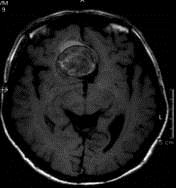

问题 病历摘要:??患者男性,56岁,因右侧视力下降伴视野缺损2个月来院就诊,诉头痛,无明显头晕,无视物重影,无恶心呕吐,无肢体抽搐,无肢体乏力,胃纳佳,大小便正常,既往史无特殊,入院检查:神志清楚,言语清楚,体毛分布正常,左侧视力4.6,右侧视力4.0,粗侧右颞侧视野缺损,左侧正常,颈软,四肢肌张力正常,肌力正常,病理征(-)。 结合影像学,考虑诊断为??提示:入院检查内分泌激素正常,为明确诊断,检查头部?MRI,如右图所示。

选项 A.鞍结节脑膜瘤 B.垂体腺瘤 C.颅咽管瘤 D.动脉瘤 E.胆脂瘤 F.异位松果体瘤

答案 D